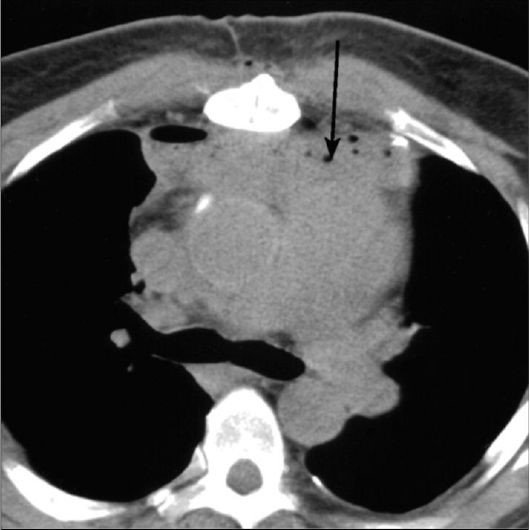

Sepsisli xəstələrdə rentgenoloji müayinədə mediastinumda hava görünməsi yüksək şübhə əlamətidir (Şəkil 9).

Şəkil 9. Mediastinal emfizema

Şəkil 10. KT. Kontrastın qida borusundan ekstravazasiyası

Kəskin mediastinitin diaqnozunu dəqiqləşdimək üçün ən vacib müayinə KT-dir. KT-də divararalığında ödem, maye, hava, kontrast ekstravazasiyası mediastinitin xarakterik əlamətləridir.

- KT-də divararalığında ödem, maye, hava, bəzən də kontrast ekstravazasiyası (Şəkil 10)